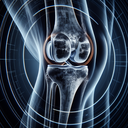

МРТ колінного суглобу

МРТ колінного суглоба – це неінвазивна діагностична процедура, яка використовує магнітне поле та радіочастотні хвилі для отримання детальних зображень структури коліна. Цей метод є особливо корисним для оцінки стану м'яких тканин, таких як зв’язки, м’язи, хрящі та меніски. ### Коли призначають МРТ колінного суглоба: 1...